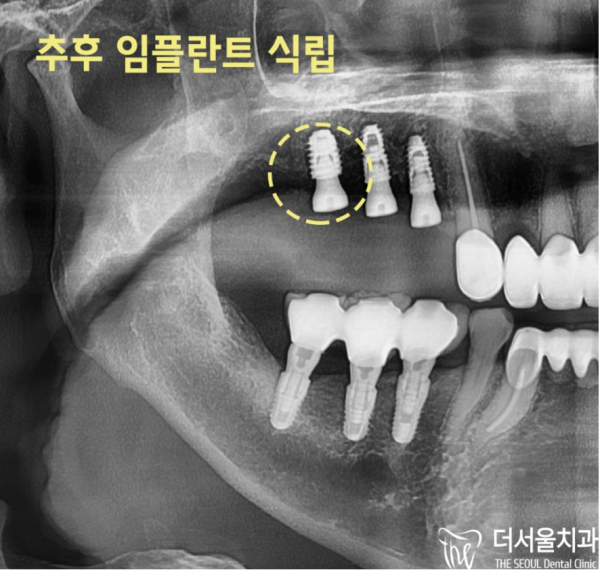

이 환자분은 14, 15번의 작은 어금니부터 픽스처를 식립하면서 16번 부위에 뼈이식을 하고

뼈이식이 잘 마무리되면 그때 16번 부위에 픽스쳐를 식립하기로 하였습니다.

This patient has been implanting bone grafts on site 16 starting with 14 or 15 small molars

When the bone transplant is completed well, we decided to implant the fixture in area 16.